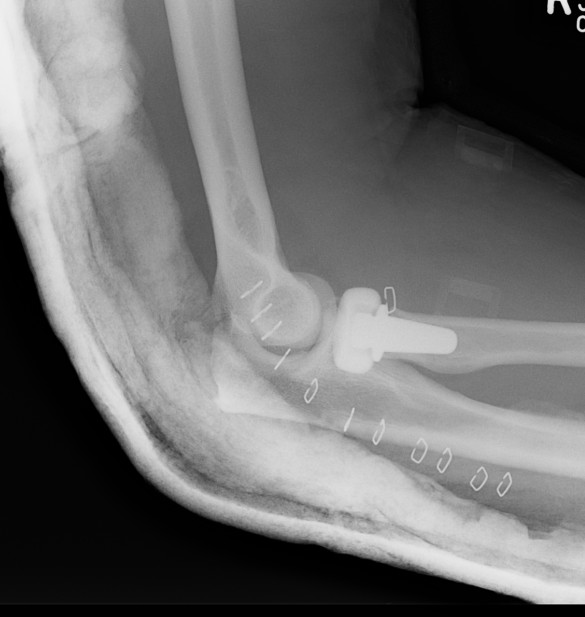

Elbow dislocation with radial head fracture

Management

Critical to elbow stability

Based upon Mason classfication

Terrible Triad

Definition

Elbow dislocation with radial head fracture + coronoid fracture + MCL tear

Technique

Radial head replacement with lag screw fixation of Type II coronoid

Radial head replacement with lasso fixation of small coronoid fragment